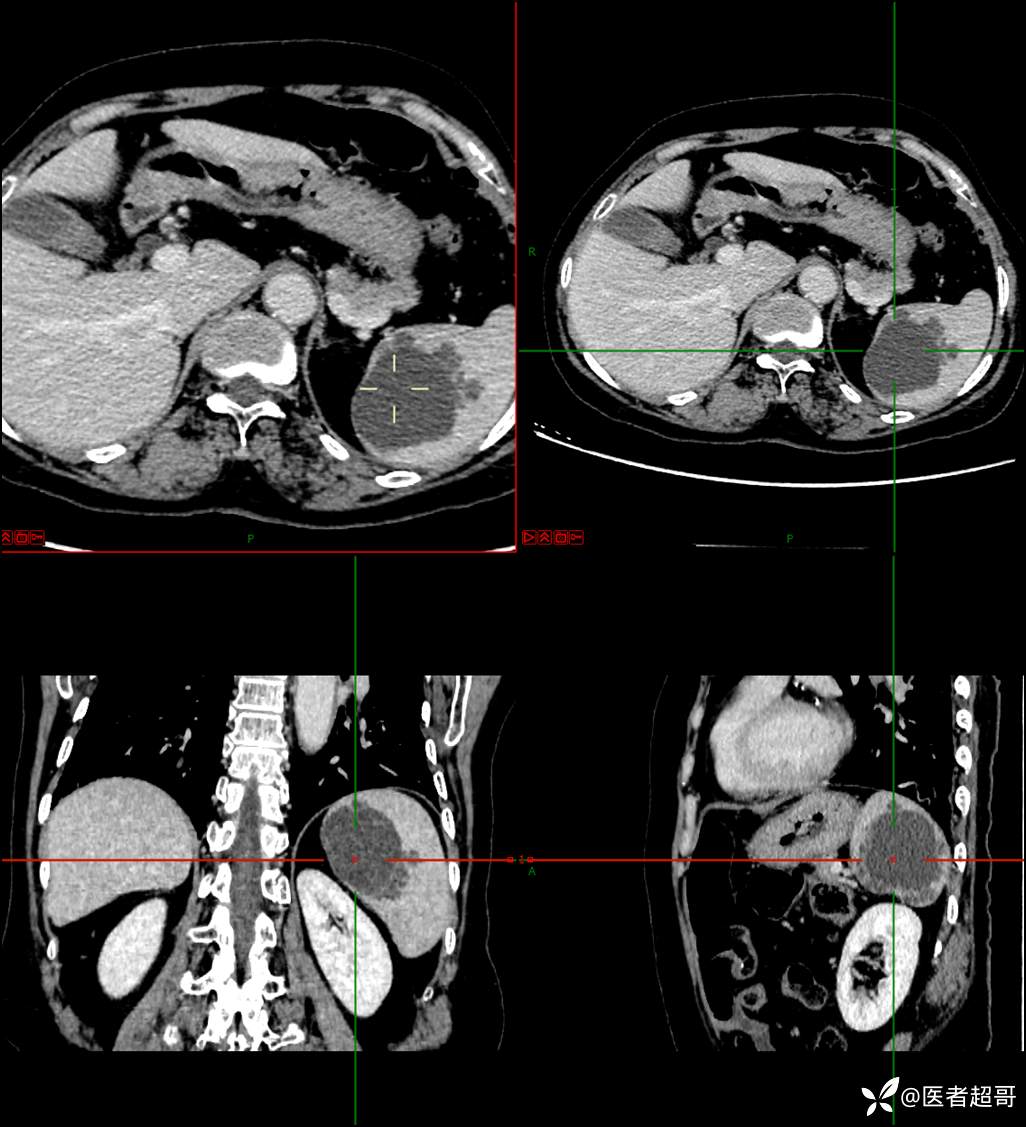

【影诊笔记598】脾脏占位03,脾脏囊性占位,回帖即可查询病理,请分析!

现病史:患者9天前于市人民医院查体时发现脾脏肿物,未行处理,后于我院门诊查,上腹部CT平扫+强化:脾脏占位,考虑良性,囊肿?脉管源性病变?患者诉平素无异常不适。现患者为求进一步诊疗,门诊遂以“脾肿物”收入院。患者自患病以来,神志清,精神可,饮食、睡眠可,大小便正常,体重未见明显变化。